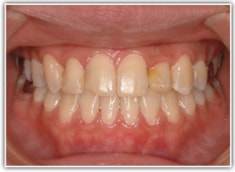

反対咬合ケース

治療法:表の矯正(T21ブラケット)

治療前